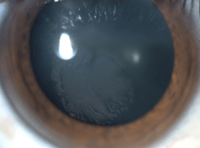

La agudeza visual (AV) no corregida fue de movimientos de mano en el OD y de 0.4 (mejora a 0,5 con agujero estenopeico) en su ojo izquierdo (OI). Las maniobras de confusión encaminadas a descubrir la pérdida de visión funcional fueron negativas. La córnea derecha presentó una opacidad del epitelio central (Figura 1) con múltiples microquistes diminutos, márgenes bien delimitados en forma de "plumas" y con patrón de espiral. La tinción con fluoresceína fue negativa. La córnea izquierda era completamente normal así como el resto de la exploración ocular.

Figura 1. Opacidad corneal central con patrón arremolinado y bordes plumosos formados de microquistes apretados. Nótese la extensión al limbo nasal inferior.